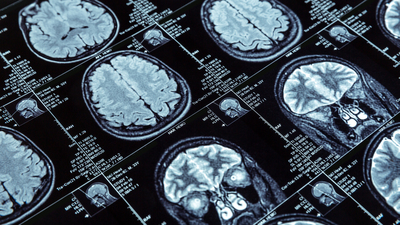

Ani gelişen denge kaybı ve mide bulantısı şikayetleriyle nöroloji servisine başvuran Begüm Kılıç’ın muayene ve tetkiklerin ardından beyin damarlarında tıkanıklık olduğu tespit edildi.

Kılıç, durumunun müdahale edilmesi gereken ciddi bir sağlık sorunu olabileceğini anladığında 3 gün geçtiğini aktararak şunları söyledi: "3 gün sonra bir nöroloji uzmanına başvurdum. Doktorum muayene ve MR incelemelerini yaptı. MR sonuçlarına göre beyin damarlarımda tıkanıklık olduğu ortaya çıktı. Hastane yatışım yapıldı ve tedavime başlandı. Taburcu edildikten sonra da denge fizyoterapisi ve medikal tedavim devam etti. Şimdi kendimi çok daha sağlıklı hissediyorum; dengemi koruyabiliyor ve daha net konuşabiliyorum. Günlük işlerimi yapıyor, ailem ve dostlarımla vakit geçirebiliyorum."

Uzm. Dr. Mustafayev, “Beynin bir kısmına giden kan akışı azaldığında veya kesintiye uğradığında, beyin dokusunun oksijen ve besin almasını önleyen bir inme (felç) meydana gelir ve beyin hücreleri dakikalar içerisinde ölmeye başlar. İnmenin oluştuğu bölgedeki fonksiyonlarda geçici ya da kalıcı kayıplar oluşur. Bu nedenle erken müdahale oldukça önemlidir. Özellikle konuşmada bozulma, dengesizlik, vücudun bir tarafında uyuşma veya güçsüzlük, çift görme gibi belirtiler hissedildiği an, ilk 4 saat içerisinde ‘İNME’ şüphesi ile 112 Acil Çağrı Merkezi’nin aranması gerekmektedir. Hastamız Begüm Kılıç, belirtileri başladıktan 3 gün sonra tarafımıza başvurdu. Daha vahim bir tabloya dönüşmeden hastaya gerekli müdahaleleri yaptık ve tedavisine başladık. Böylece olası beyin hasarını ve diğer komplikasyonları azaltmak mümkün olabildi. Etkin tedaviler sayesinde felçten kaynaklı sakatlığın önlenmesi sağlanmış oldu” diye konuştu.